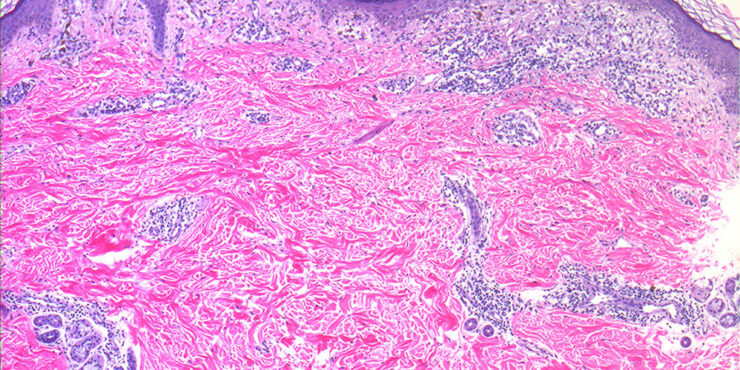

Arsenical keratoses = التقران الزرنيخي ARSENICAL KERATOSES Arsenical keratoses (ArKs) are precancerous lesions found in association with chronic arsenicism. These lesions have the potential to develop into invasive SCC. Arsenic is a ubiquitous element that has no color, taste, or odor. It has the potential to cause characteristic acute and chronic syndromes in persons exposed […]